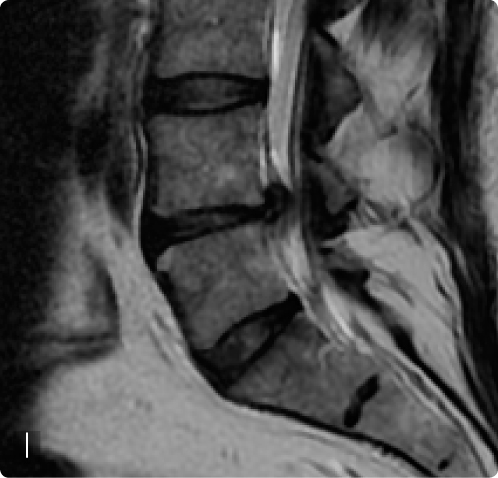

L’indicazione chirurgica è stata occasionalmente posta anche in presenza di sindromi da ernia del disco in pazienti non artrosici (i,l), qualora si fossero presentati all’osservazione in fase compressiva o deficitaria, o in fase irritativa qualora vi fosse una resistenza alla terapia conservativa.